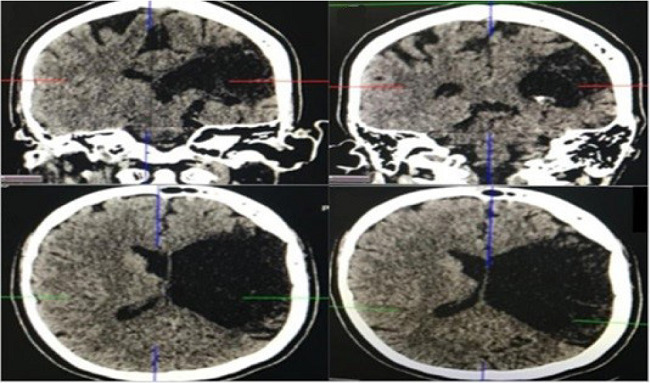

Question E. Considering that the neurological sequel presented by the patient could be of embolic vascular origin secondary to heart disease and not due to poliomyelitis, as believed at admission, because it was only in the right arm, a cranial computed tomography scan was performed. This examination revealed lesions suggestive of chronic ischemia in the left parietal, temporal, and frontal lobes, thereby confirming the suspicion of vascular etiology (Figure 5).